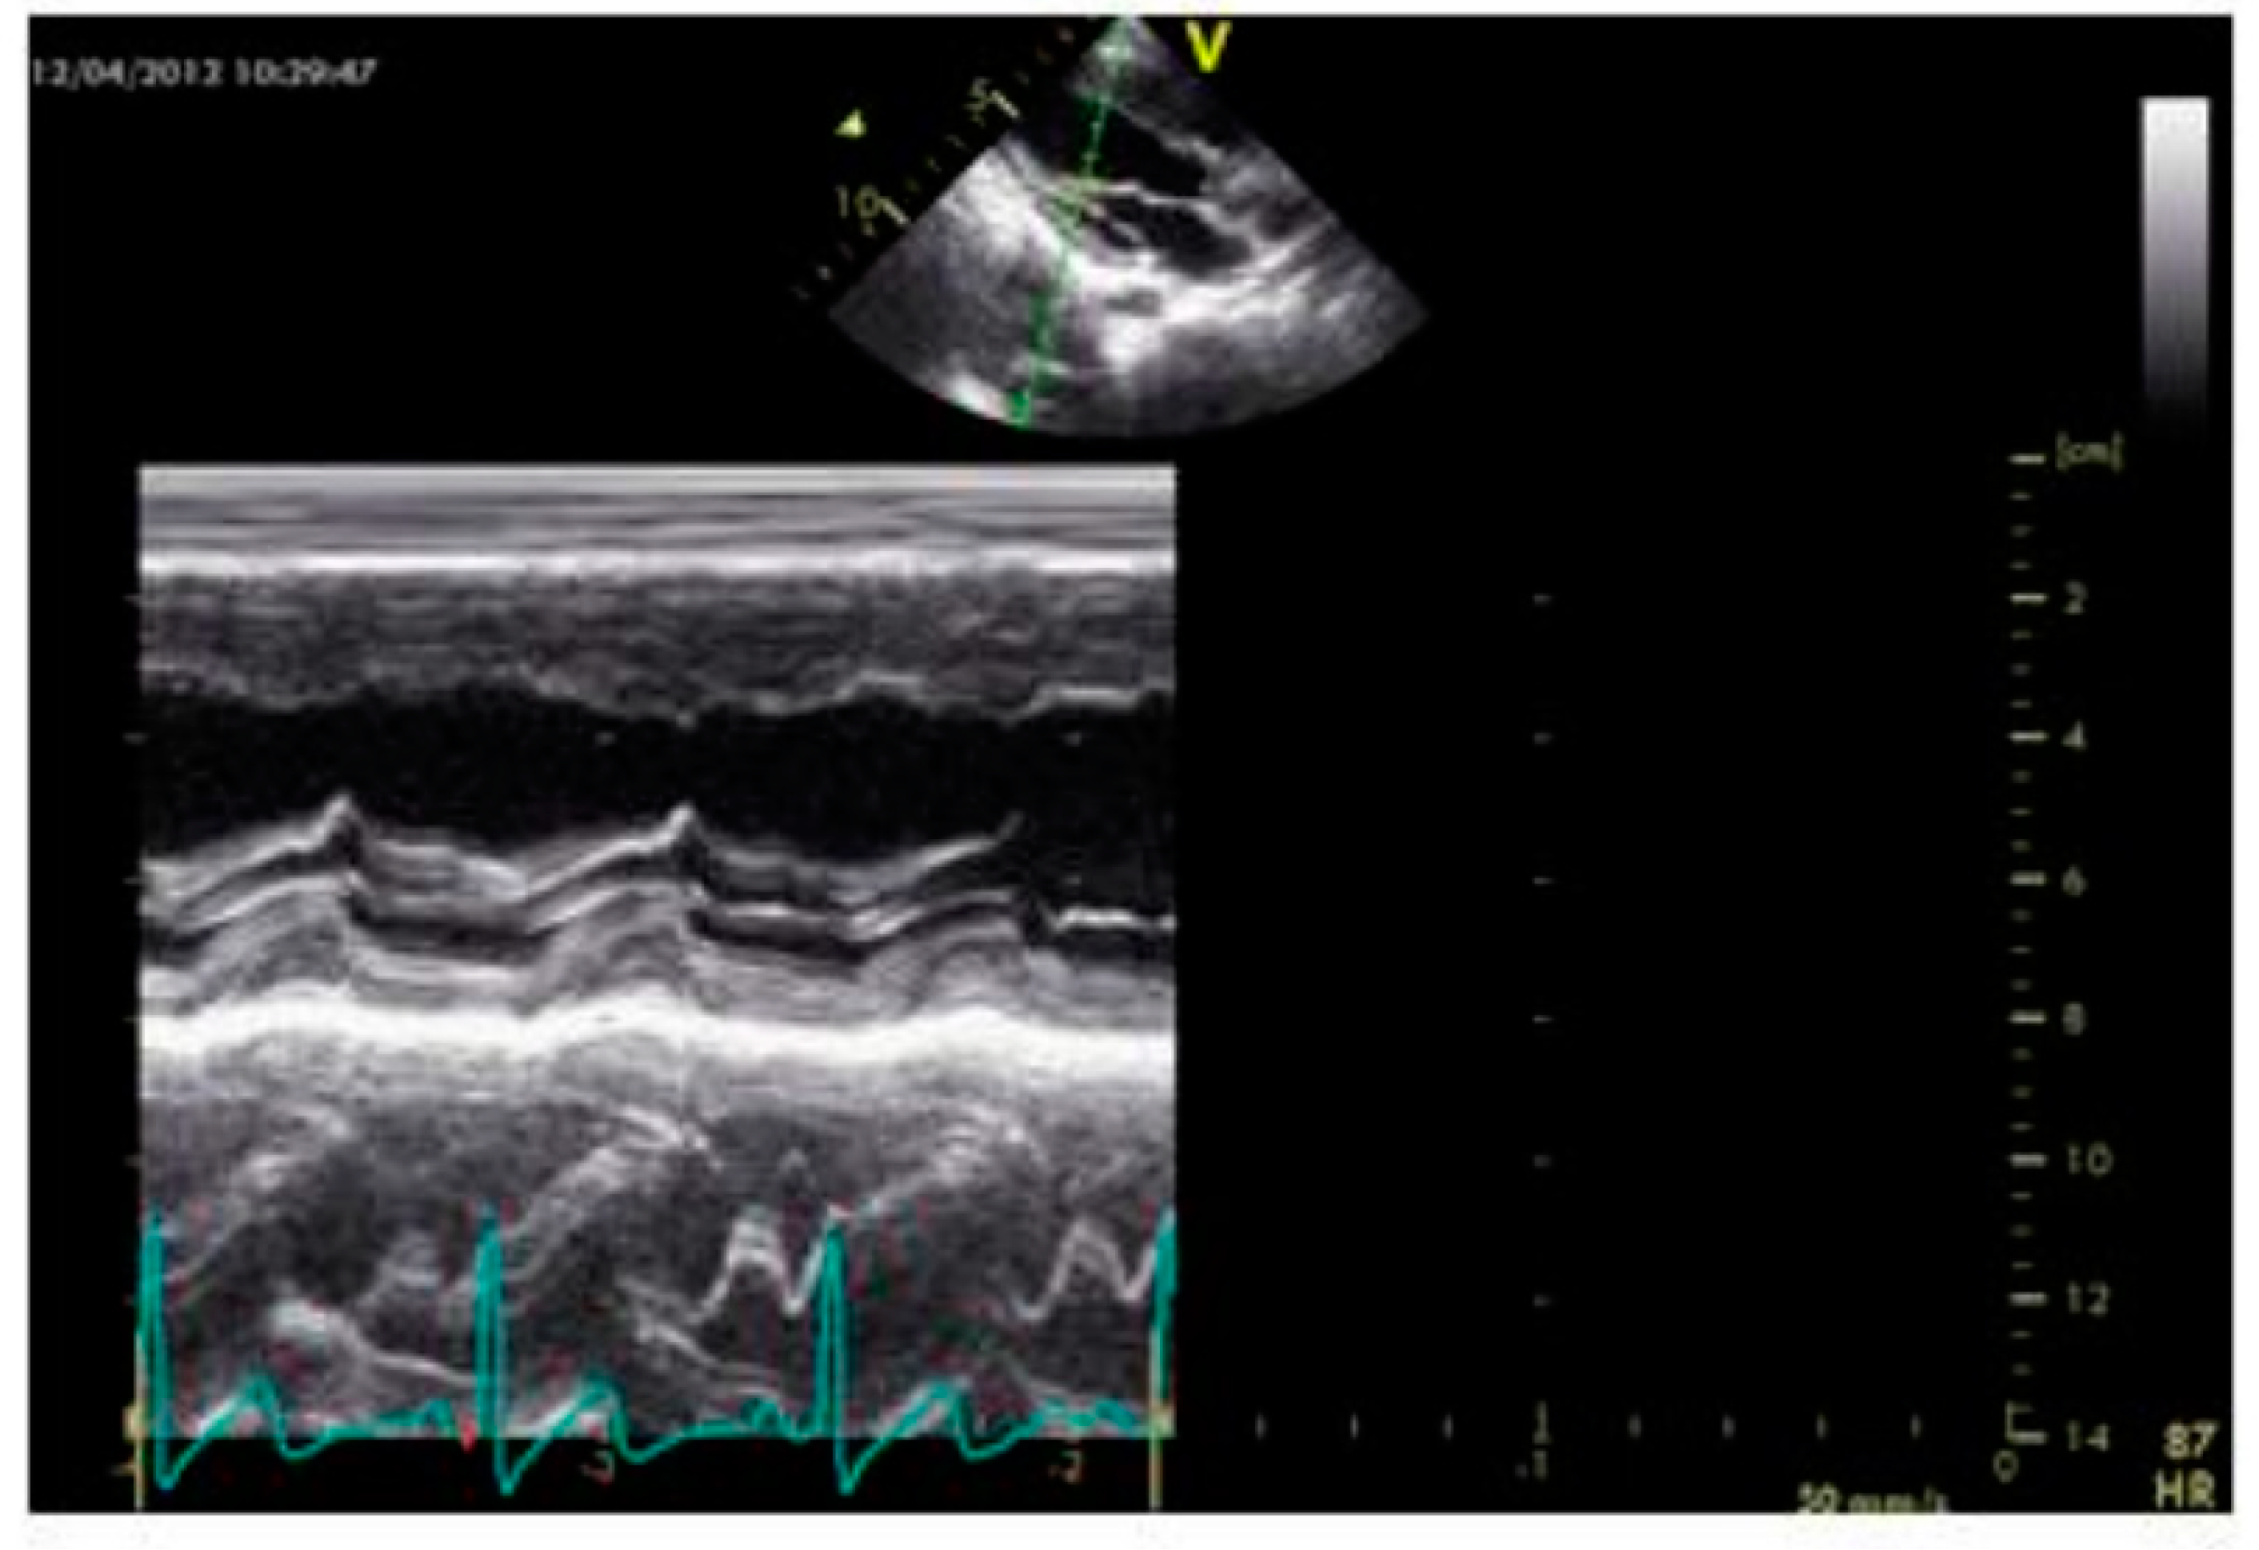

2.2. Echocardiography